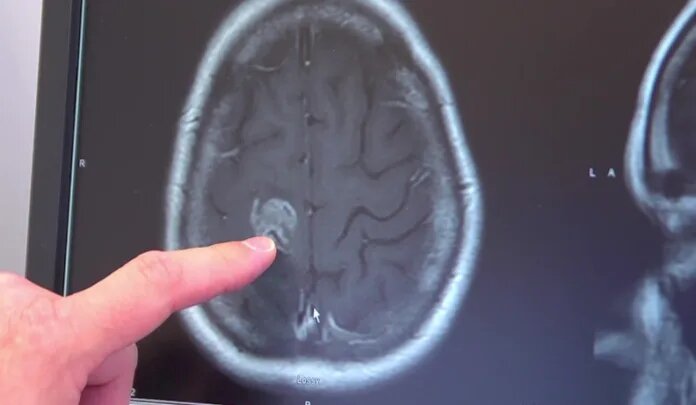

Neurology: грязный воздух увеличивает вероятность развития опухолей мозга

Длительное воздействие загрязненного воздуха может способствовать повышению риска развития менингиомы — одной из самых распространенных опухолей центральной нервной системы. К такому выводу пришли ученые из Датского института онкологии, проанализировав сведения почти о 4 миллионах человек в течение 21 года. Их исследование опубликовано в журнале Neurology.

Менингиома обычно представляет собой доброкачественное новообразование, которое развивается в оболочках головного и спинного мозга. Исследователи выяснили, что у людей, которые в течение десятилетия жили в условиях повышенного содержания в воздухе ультрамелких частиц, диоксида азота и других загрязнителей, риск появления этой опухоли значительно возрастал. Например, увеличение концентрации частиц PM2.5 всего на 4 мкг/м³ приводило к росту вероятности заболевания на 21%.

При этом ученые уточняют, что их выводы указывают на статистическую связь (корреляцию), а не на доказанную причинно-следственную зависимость. Однако результаты подтверждают предположение, что загрязнение воздуха опасно не только для легких и сердечно-сосудистой системы, но и для мозга. Особенно учитывая, что ультрамелкие частицы способны проникать через гематоэнцефалический барьер, который обычно защищает мозг от вредных веществ.

Авторы работы подчеркивают необходимость дальнейших исследований, чтобы разобраться в механизмах этого воздействия и разработать меры профилактики. Если гипотеза подтвердится, то борьба с загрязнением воздуха приобретет еще более весомое значение — уже как способ снизить риск развития опухолей мозга.